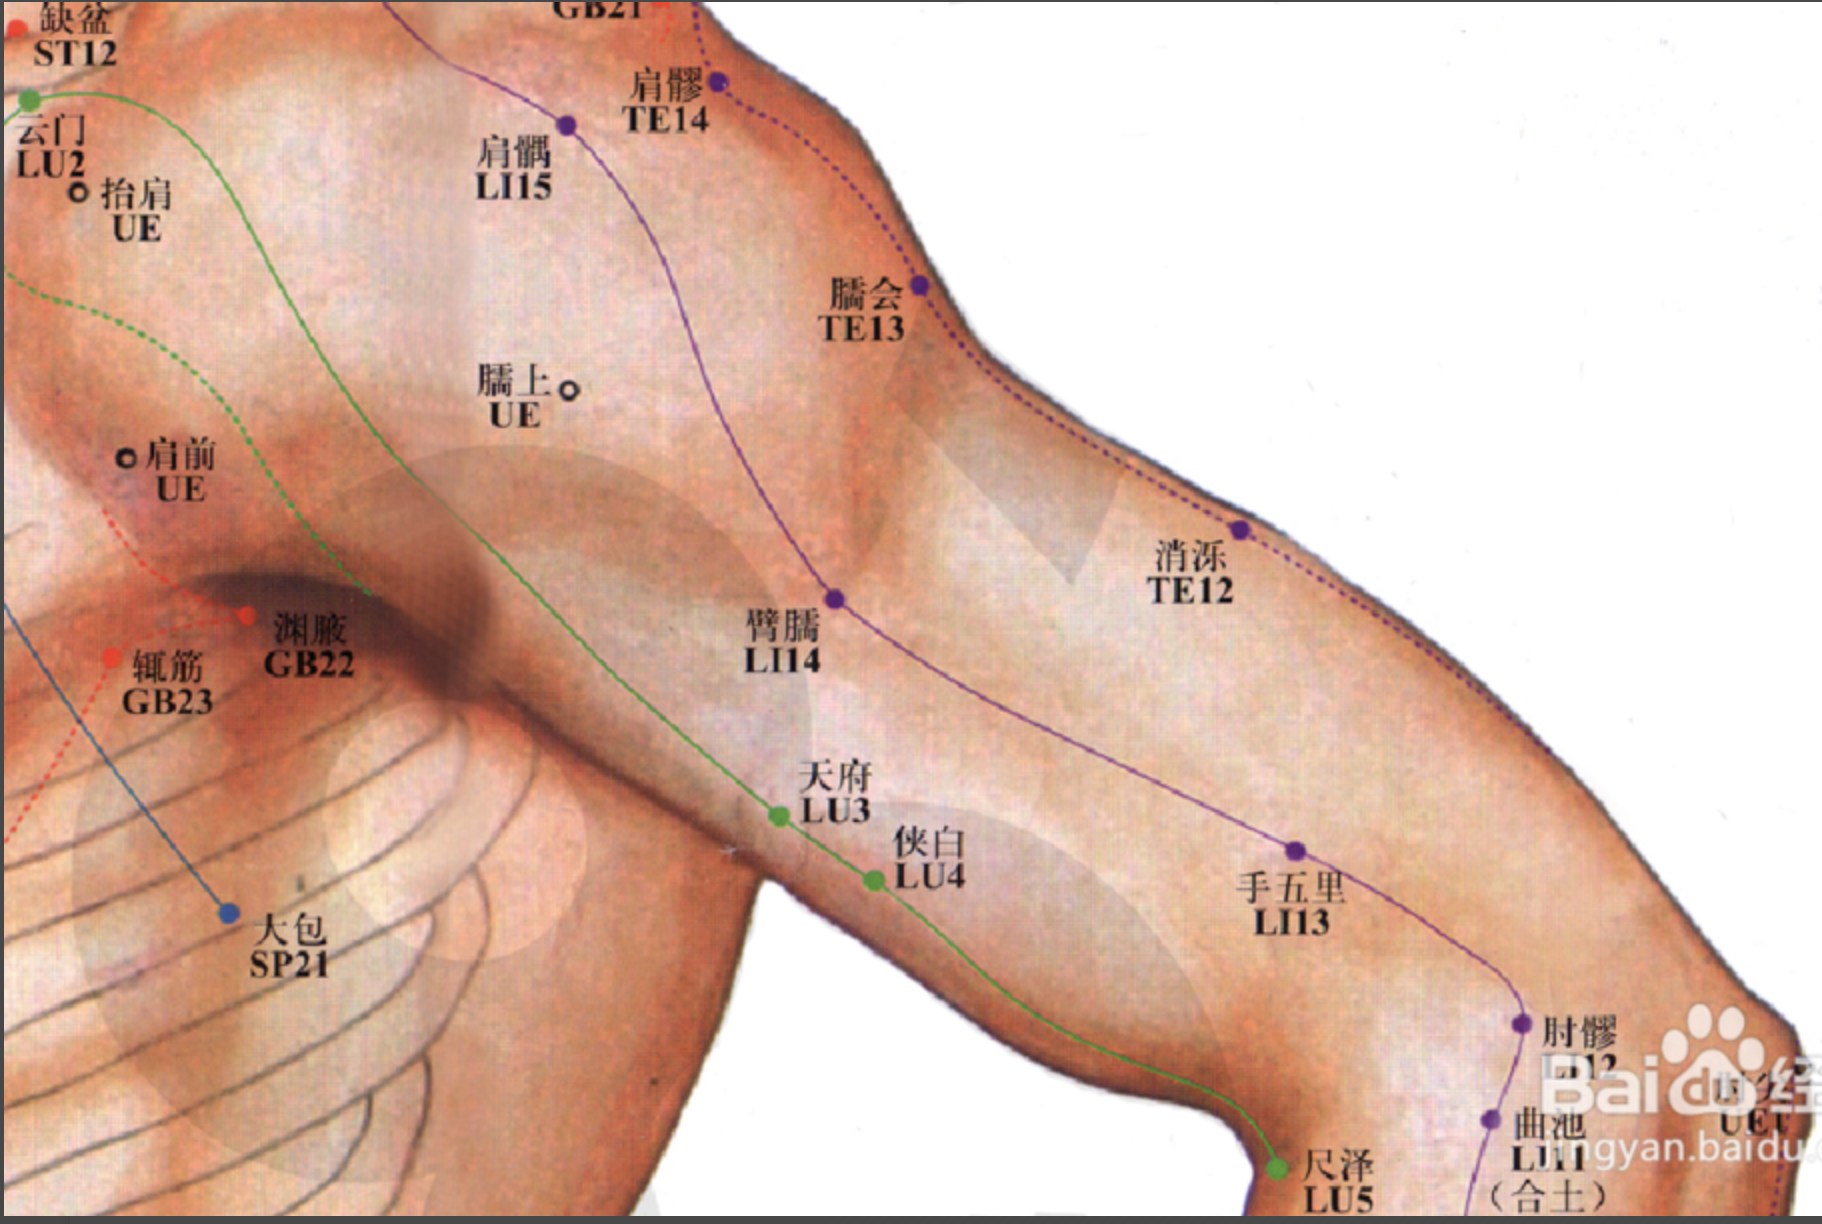

【(二)手阳明大肠经(图10-20-1)】

2、歌诀 手阳明穴起商阳,二间三间合谷藏,阳溪偏历历温溜,下廉上廉三里长,曲池肘髎(liáo)迎五里,臂臑(nào)肩髎(liáo)巨骨起,天鼎浮突接禾髎(liáo),终以迎香二十止。

3、经脉循行 起于食指末端(商阳),沿食指外(桡)侧向上,通过一、二掌骨之间(合谷)向上进入两筋(拇长伸肌腱与拇短伸肌腱)之间的凹陷处,沿前臂前方,至肘部外侧,再沿上臂外侧前缘,上走肩端(肩髃(yú)),沿肩峰前缘向上出于颈椎(大椎),再向下入缺盆(锁骨上窝)部,联络肺脏,通过横膈,属于大肠。

缺盆部支脉:上走颈部,通过面颊,进入下齿龈,回绕止上唇,交叉于人中,左脉向右,右脉向左,分布在鼻孔两侧(迎香),与足阳明胃经相接。

从食指末端起始(商阳),沿食指桡侧缘(二间、三间),出第一、二掌骨间(合谷)、进入两筋(拇长伸肌腱和拇短伸肌腱)之间(阳溪),沿前臂桡侧(偏历、温溜、下廉、上廉、手三里),进入肘外侧(曲池、肘髎),经上臂外侧前边(手五里、臂臑),上肩,出肩峰部前边(肩髃、巨骨,会秉风),向上交会颈部(会大椎),下入缺盆(锁骨上窝),络于肺,通过横膈,属于大肠。

它的支脉:从锁骨上窝上行颈旁(天鼎、扶突),通过面颊,进入下齿槽,出来挟口旁(会地仓),交会人中部(会水沟)--左边的向右,右边的向左,上夹鼻孔旁(锁骨上窝),络于肺,通过横膈,属于大肠。

4、主要证候 腹痛、肠鸣、泄泻、便秘、咽喉肿痛、齿痛。本经循行部位疼痛、热肿或寒冷麻木等。

5、主治概要 主治头面、五官、咽喉病、热病及经脉循行部位的其他病证。

【(十)手少阳三焦经(图10-28)】

2、歌诀 二十三穴手少阳,关冲液门中渚旁。阳池外关支沟正,会宗三阳四渎长。天井清冷渊消泺(luò),臑会肩髎天髎堂。天牖(yǒu)翳风瘛(chì)脉青,颅息角孙丝竹空。和髎耳门听有常。

3、经脉循行 起于无名指末端(关冲)上行于第 4、5掌骨间,沿腕背、出于前臂外侧尺桡骨之间,经肘尖沿上臂外侧达肩部,交大椎,再向前入缺盆部,分布于胸中,络心包,过膈,从胸至腹,属于上、中、下三焦。

胸中支脉:从胸向上出于缺盆部,上走项部,沿耳后直上至额角,再下行经面颊部至目眶下。

耳部支脉:从耳后入耳中,出耳前,与前脉交叉于面颊部,到目外眦,与足少阳胆经相接。

4、主要病候 腹胀、水肿、遗尿、小便不利、耳聋、咽喉肿痛、目赤肿痛、颊肿、耳后、肩臂肘外侧痛等。

5、主治概要 主治侧头、耳、目、胸胁、咽喉病、热病及经脉循行部位的其他病证。

肩髎

【定位】 在肩部,肩髃(yú)后方,当臂外展时,于肩峰后下方呈现凹陷处。

【主治】 臂痛,肩重不能举。

【配伍】 配天宗、曲垣(yuán)治疗肩背疼痛;配肩井、天池、养老治上肢不遂、肩周炎。

【刺灸法】 直刺 0.5 ~ 1 寸;可灸。